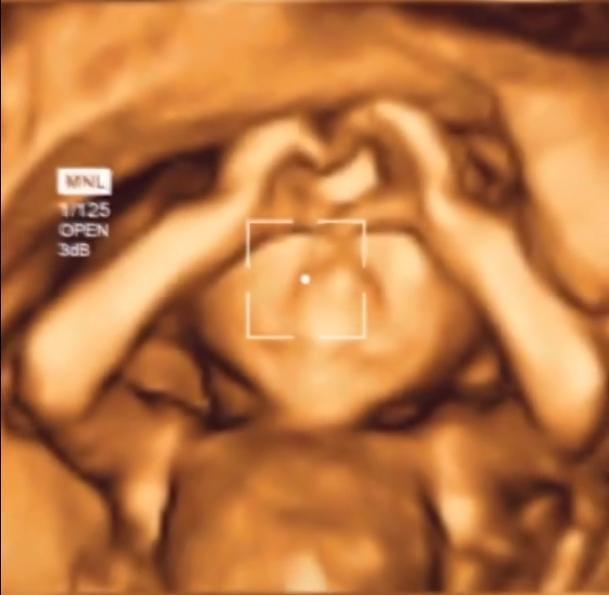

四维彩超|孩子腹中“比心”火了,四维彩超下的孩子动作暖心,医生:太有爱

到了医院做好了一切准备,当四维彩超的镜像画面显示出肚子里胎儿的时候,这让李先生和妻子都大吃一惊。因为肚子里的宝宝非常清楚地用小手在和父母比心。简直是在用这样的方式告诉父母自己发育的非常健康,让父母放心只等着接下来的见面就好了。

这哪是还在发育中的胎儿啊,简直就是一个活脱脱的小大人,李先生赶紧把这珍贵的画面拍摄了下来传到了网上,也让网友共同感受一下这份喜悦。医生也禁不住感叹:这太有爱了吧,想必以后也是幸福的一家。这也让李先生和妻子十分欣慰,因为这好像是世间绝无仅有的珍贵礼物,这也一定是位天使宝宝,也越来越期待和孩子的见面。